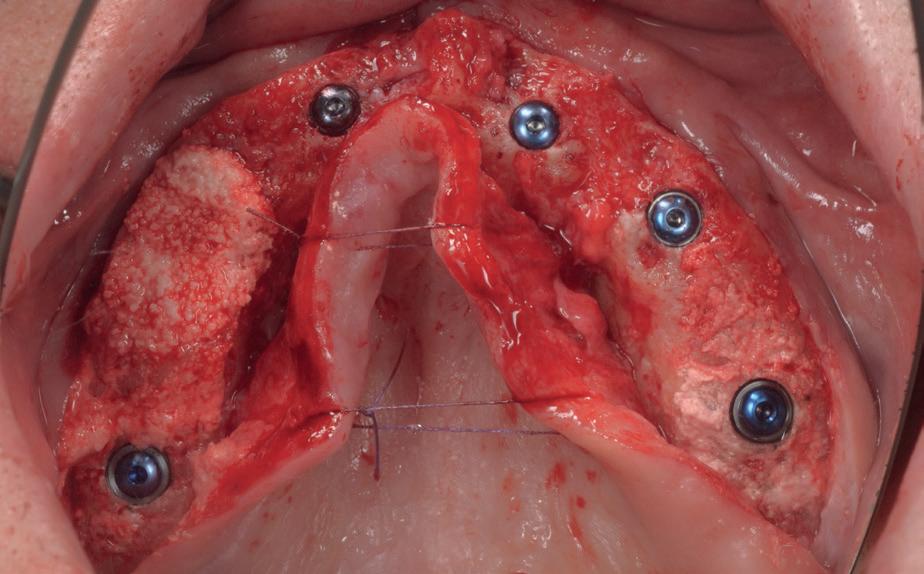

Chirurgie plaatsen van de 6 implantaten

Voor de behandeling kreeg de patiënt Amoxicilline 500mg 3dd1 gedurende een week voorgeschreven waarbij er een dag voor de chirurgie gestart werd, als pijnstilling Ibuprofen 600 mg 3dd1 voor een week en Blue M Mouthwash voor de mondspoeling gedurende de eerste 2 weken. Na de anesthesie werd een incisie gemaakt van tuber tot tuber en werd de

3. Na flap een guide pin in foramen incisivum

4. Plaatsen van 6 implantaten en kaakverbreding 14

5. Primaire sluiting met een door-

mucosa zowel buccaal als palatinaal afgeschoven. Het is belangrijk om te realiseren dat de bovenkaak zachter alveolair bot heeft dan de onderkaak en dat stug periost op de kaak kan zitten. Daarom is het van belang om te starten met curettage van de kaak. Na het vrijleggen van de canalis incisivum, werd een guide pin in de canalis geplaatst. Het kanaal loopt loodrecht op de kaak en kan dienen als referentie

lopende hechting

6. Tweede fase chirurgie

7. Intraoraal scan occlusaal van de implantaten

8. Intraoraal scan met de scan

abutments

9. Digitaal design tijdelijke brug

10. Setup van tijdelijke brug in het gezicht

voor de implantaten (afbeelding 3). Hierna werd met een meetinstrument de locaties van de implantaten uitgemeten en werd een initiële osteotomie op deze locaties gemaakt. Voor de 16 werd een crestale sinusbodemelevatie met Densah boren uitgevoerd. Hierbij werd het zachte bot gecondenseerd om naar crestaal geduwd te worden, waarna het membraan van Schneider meelifte. Door de osteotomie werden 1cc botkorrels geplaatst en daarna direct het implantaat. Ter plaatse van de 14 zat een verticaal botdefect, na plaatsen van dit implantaat, werd de kaak verticaal verhoogd. Er werden 6 implantaten van het merk AnyRidge (MegaGen Implant Company, Korea) geplaatst met diameter 5.0 mm aan de distale zijdes, diameter 4.5 mm bij de premolaren en 4.0 mm implantaten bij de laterale incisieven (afbeelding 4).

Ter plaatste van de 16 en 14 werden verticale matrashechtingen geplaatst, waarna er één doorlopende hechtingen van tuber tot tuber volgde met een 4-0 gevlochten hechtdraad (afbeelding 5). Gedurende de eerste 2 weken van de genezing is het van essentieel belang voor de wondgenezing, dat de patient geen bovenprothese draagt. Deze werd daarom ingenomen, met de uitleg dat direct dragen van de bovenprothese een nadelige invloed heeft op de genezing van de kaak, de botopbouw en de implantaten. Patiënt kwam 2 weken na de chirurgie retour voor het verwijderen van de hechtingen, waarna de binnenzijde van de bovenprothese werd uitgeslepen en voorzien werd van een softliner als nieuwe tijdelijke voering voor retentie van de bovenprothese. Vanwege de kaakverhoging en sinusbodemelevatie, werd 6 maanden genezing afgewacht van het bot en integratie van de implantaten.

Tweede fase chirurgie

Na de genezingsperiode werd eerst een OPT röntgenopname vervaardigd om de genezing van de implantaten, kaakverbreding en sinusbodemelevatie te beoordelen. Er waren geen complicaties opgetreden. Bij de tweede fase chirurgie is het van absoluut belang dat er minimaal 2-3 mm gekeratiniseerd weefsel aan de buccale zijde van de implantaten wordt verkregen, anders kan de patiënt de implantaten niet goed reinigen en door de trekkrachten van de mucosa ontstaat al gauw peri-implantaire ontstekingen en recessies. De incisie hoeft niet van tuber tot tuber te zijn, maar 2 incisies van de 16 tot de 12 en 26 tot de 22 is voldoende, waarbij de incisie genoeg gekeratiniseerd weefsel aan de buccale zijde bevat, dat naar

de buccale zijde van de implantaten wordt geduwd. Er werden 6 healing abutments van 6 mm hoogte op de implantaten geplaatst, waarna de wonden werden gehecht met een 6-0 monofilament hechtdraad. In de prothese werd een nieuwe softliner over de healing abutments geplaatst. Het weefsel dient minimaal 4 weken genezingstijd te hebben (afbeelding 6).